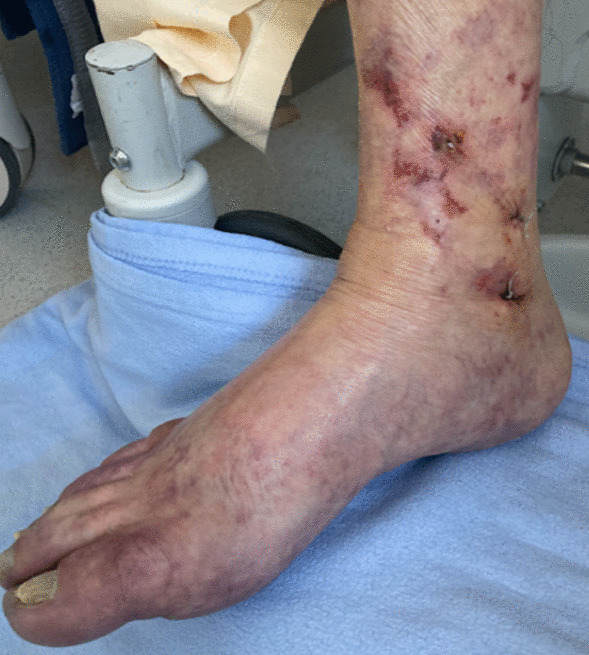

Over the following week, skin lesions on both feet, consisting of livedo associated with distal necrosis, progressed (Fig. 2). Arterial doppler of lower limbs showed no macrovascular lesion. Skin biopsy found one focus of microvascular thrombosis but neither aspect of vasculitis nor inflammatory infiltrate. Search for serum cryoglobulinemia was positive with a dosage of 5.75 mg/L, which was made of oligoclonal immunoglobulins (Ig) G, A, and polyclonal M (type IIb). Cryocrit was inferior to 1%. Oligoclonal Ig dosage was at 25 g/L (type 2). Screening for hepatitis B and C was negative. Use of epinephrine and then norepinephrine infusion during the post-CPR phase was a possible contributor to the bilateral feet distal necrosis.

Fig. 2.

Vasculitis-like skin lesions on the right foot